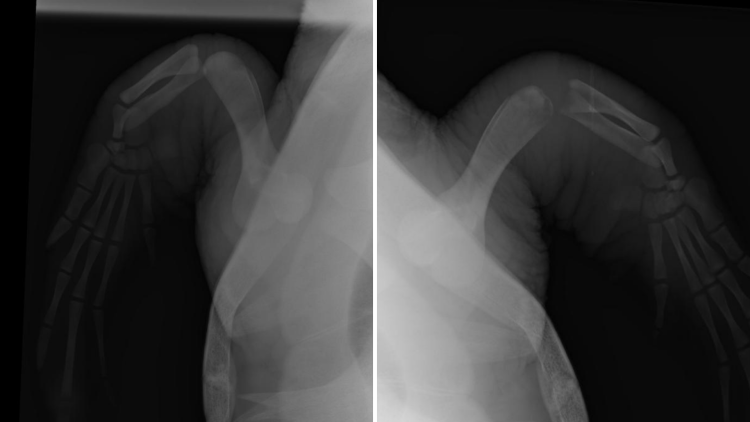

X-rays comparing Nobomvu's healthy flipper (left) to the infected one (right). Note the degradation of her "elbow" joint.

X-rays and joint samples were taken, revealing that Nobomvu has osteomyelitis, nd infection of the bone, in her right flipper. Osteolytic (bone-eating) lesions in sea turtles have been identified as a secondary effect of traumatic injuries and compromised immune systems, and we know that the stress of being stranded, as well as the injuries associated with entanglement, can and do leave sea turtles immunocompromised. Due to the slow metabolisms of sea turtles, secondary infections like this only become evident much later than we would expect in mammals.